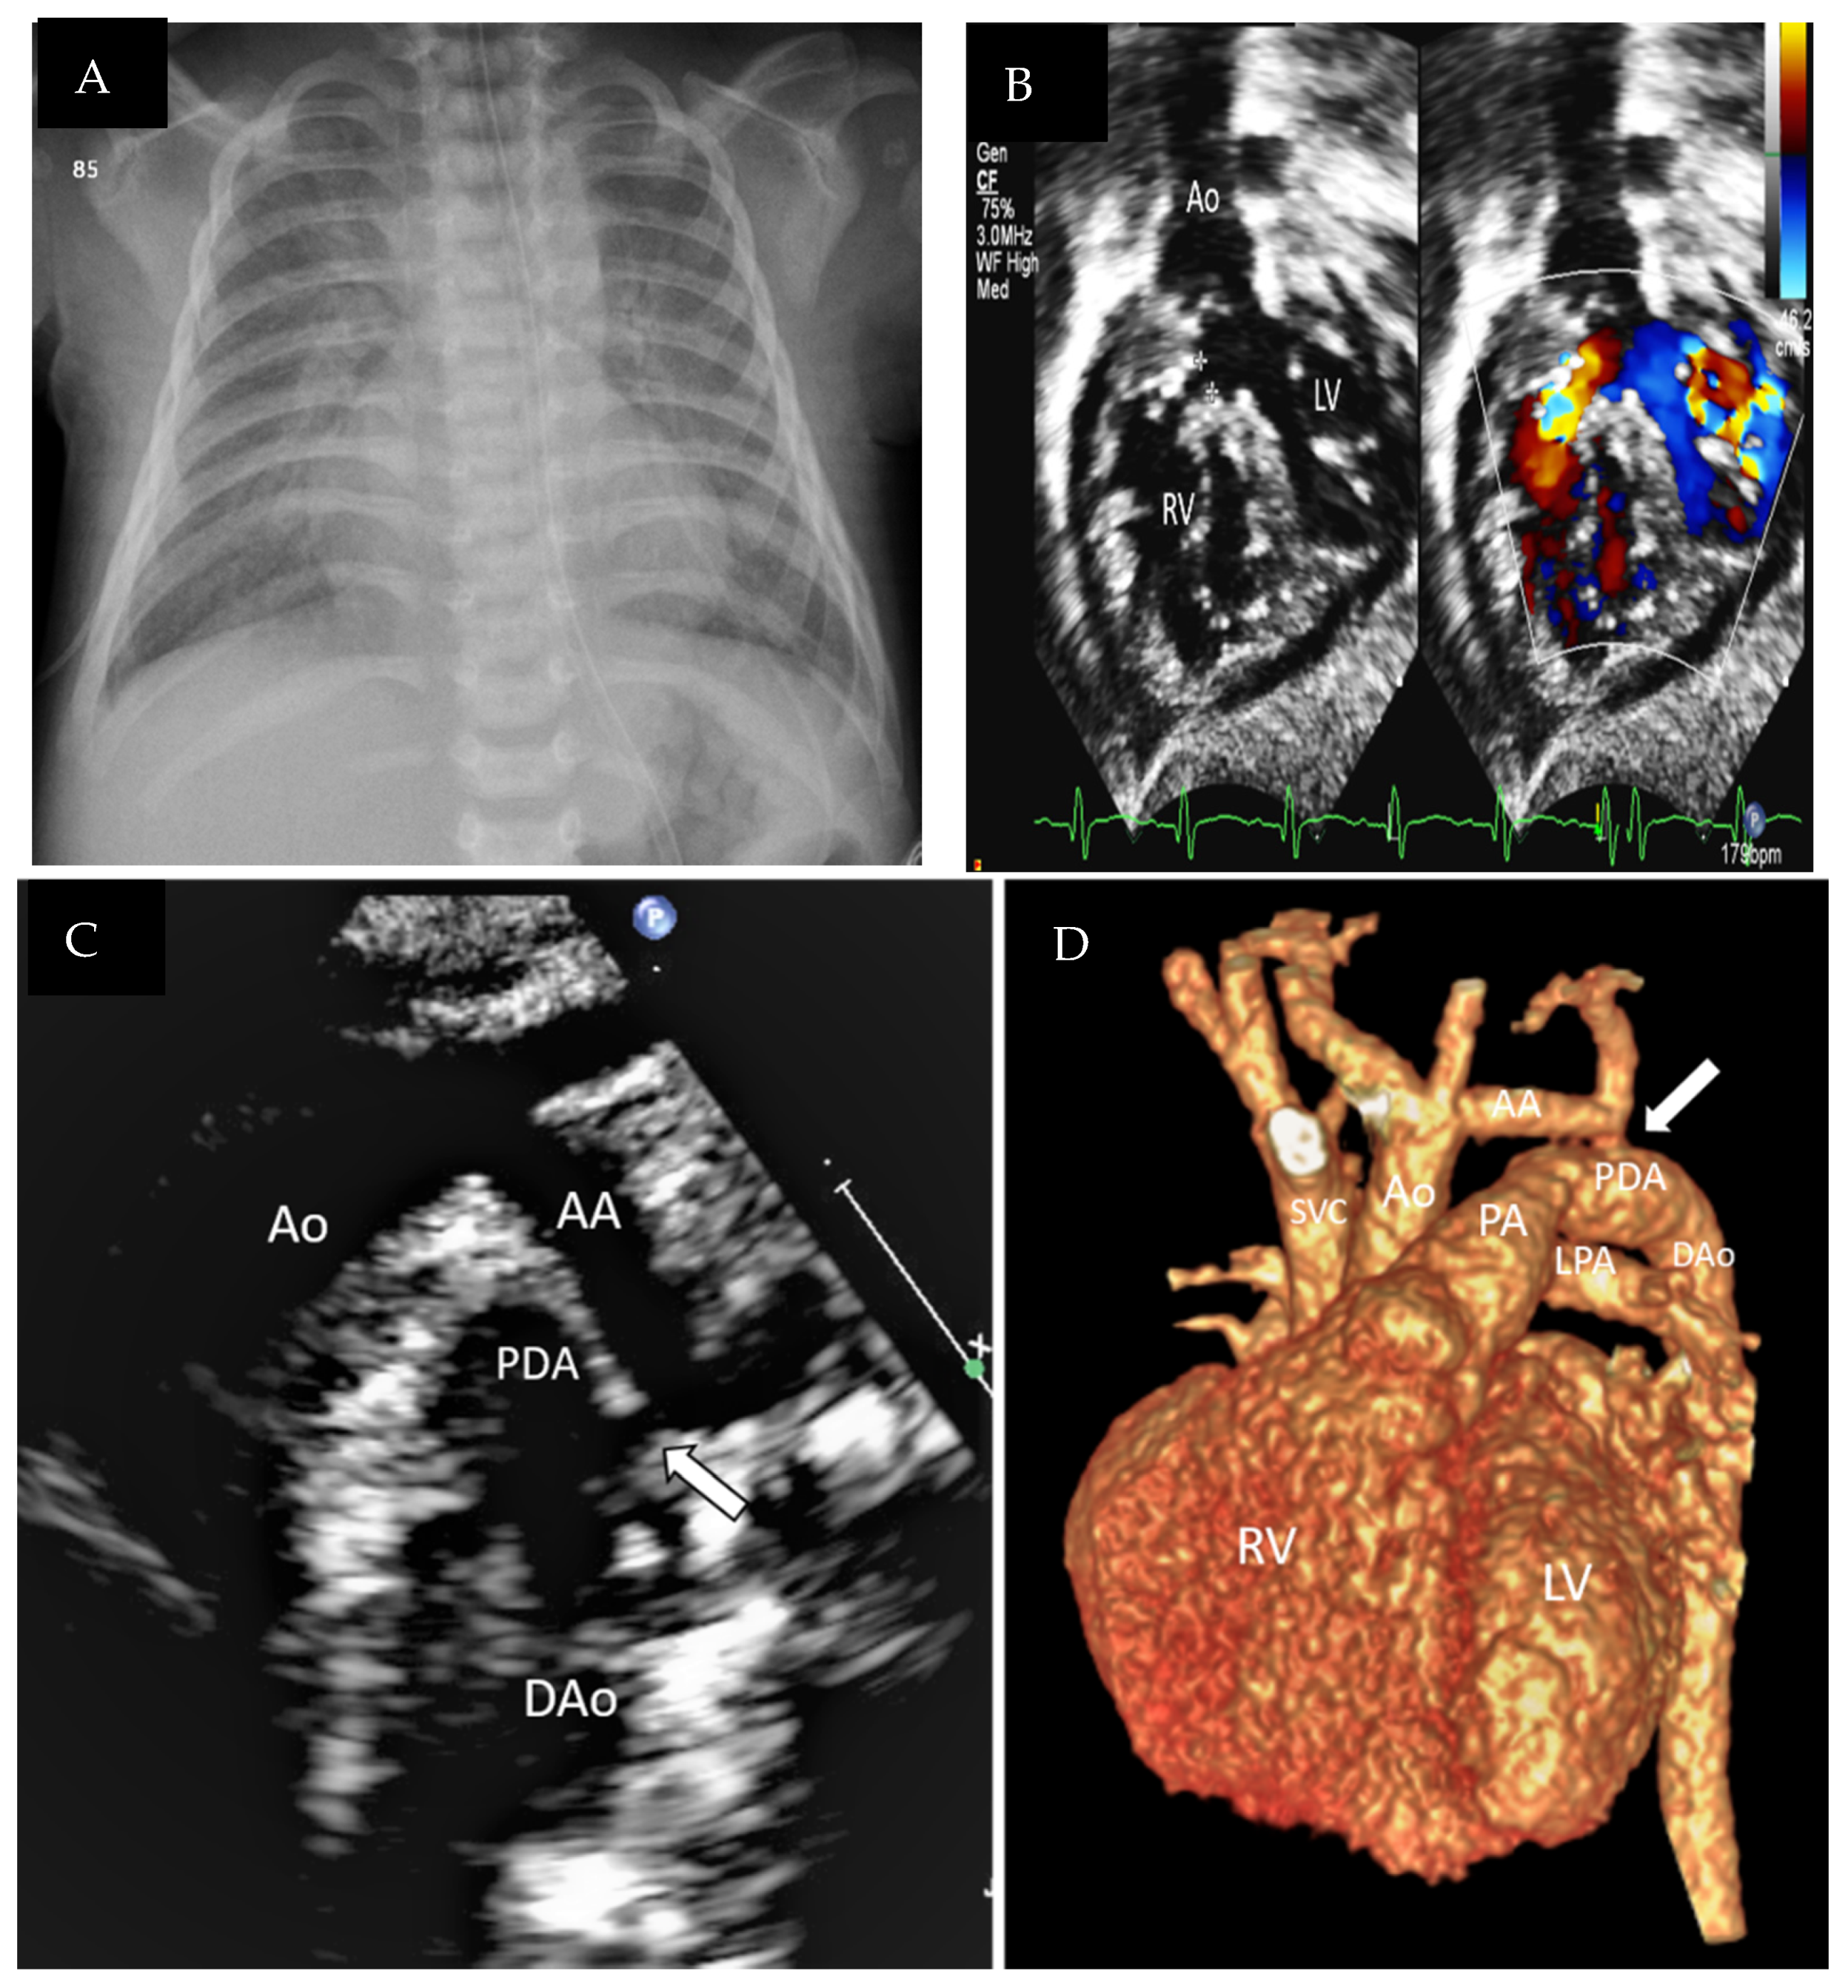

| Cardiovascular pathology | CHD in the form of severe CoA versus I.A.A., small aortic arch, P.D.A., V.S.D., small parachute-like mitral valve |

| c.280C>G:p. (Arg94Gly) | Missense point mutation | Autosomal recessive | 1 Male | Saudi | Wide fontanel, proptosis, low-set ears, talipes, hypertelorism, synophrys, lower limb abnormalities, right finger anomalies, small head, valve anomalies, severe coarctation, P.D.A., V.S.D., mild superior cerebellar vermis atrophy, congenital bilateral glaucoma | This study |